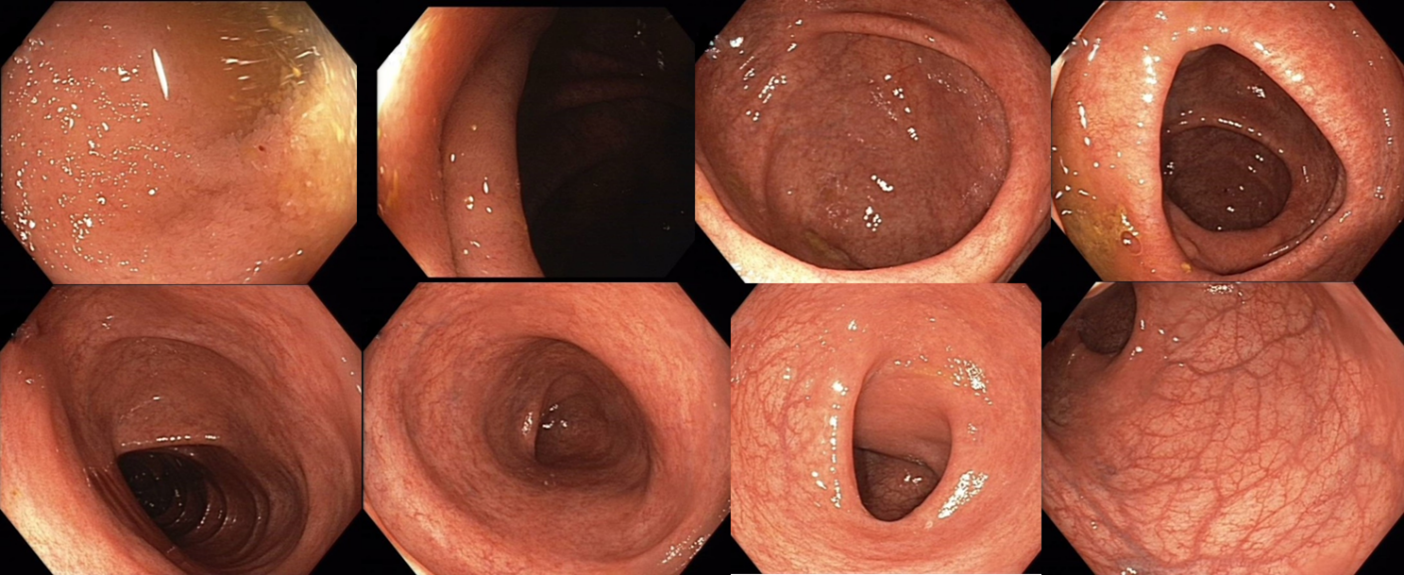

Koloskopie 2012/2: Endoskopický obraz Crohnovské pankolitidy, středně těžké až těžké (více je postižen P tračník), normální terminální ileum

2012/10 Endoskopický obraz mírné segmentální kolitidy charakteru Crohnovy choroby (rozsah postižení je 10-20 % tračníku) - podstatné zlepšení proti předchozímu nálezu, ke slizničnímu zhojení nedošlo

Koloskopie: Endoskopický obraz těžké segmentální kolitidy

2013/11 endoskopický obraz těžké pankolitidy charakteru Crohnovy choroby   - obraz cobble stones relativně je ušetřeno rektum, kde je ložiskově patrná   podslizniční cévní kresba

Koloskopie: Endoskopický kolitidy s ušetřením rekta, maximálním postižením v P tračníku – dle obrazové dokumentace zlepšení ve všech etážích tračníku   (i v P tračníku rozsah ulcerací snížen cca o 50%)

Koloskopie: edém, eroze, ulcerace, zánětlivé polypy v terénu po zánětlivých změn